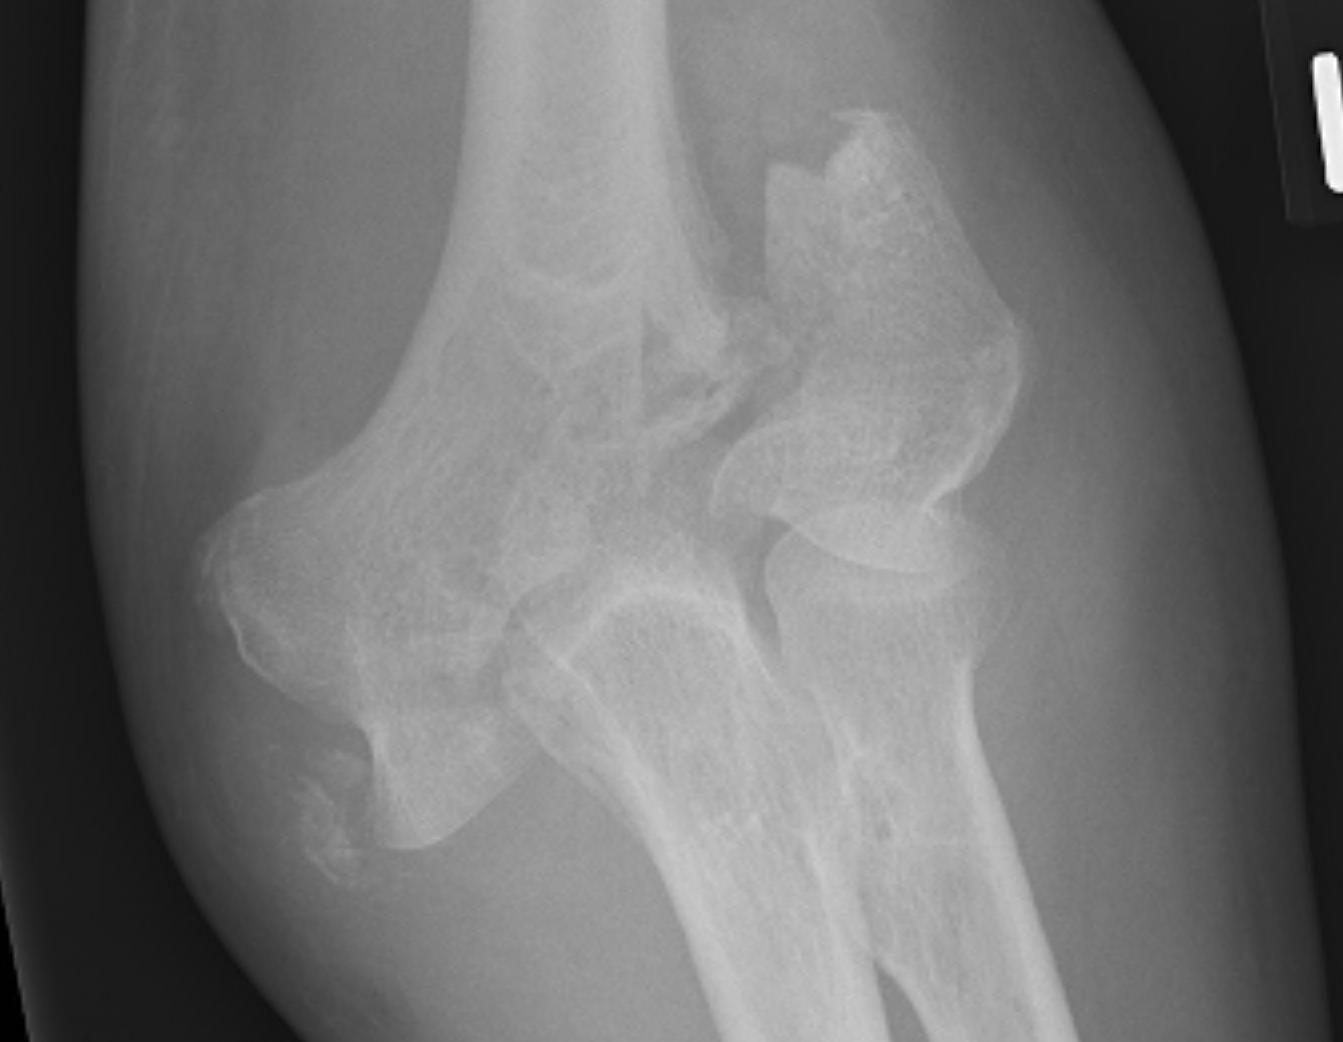

OTA / AO Classification

Type A: Extra-articular fracture

Type B: Partial articular fractures

Lateral condyle Medial condyle

Type C: Complete articular fractures